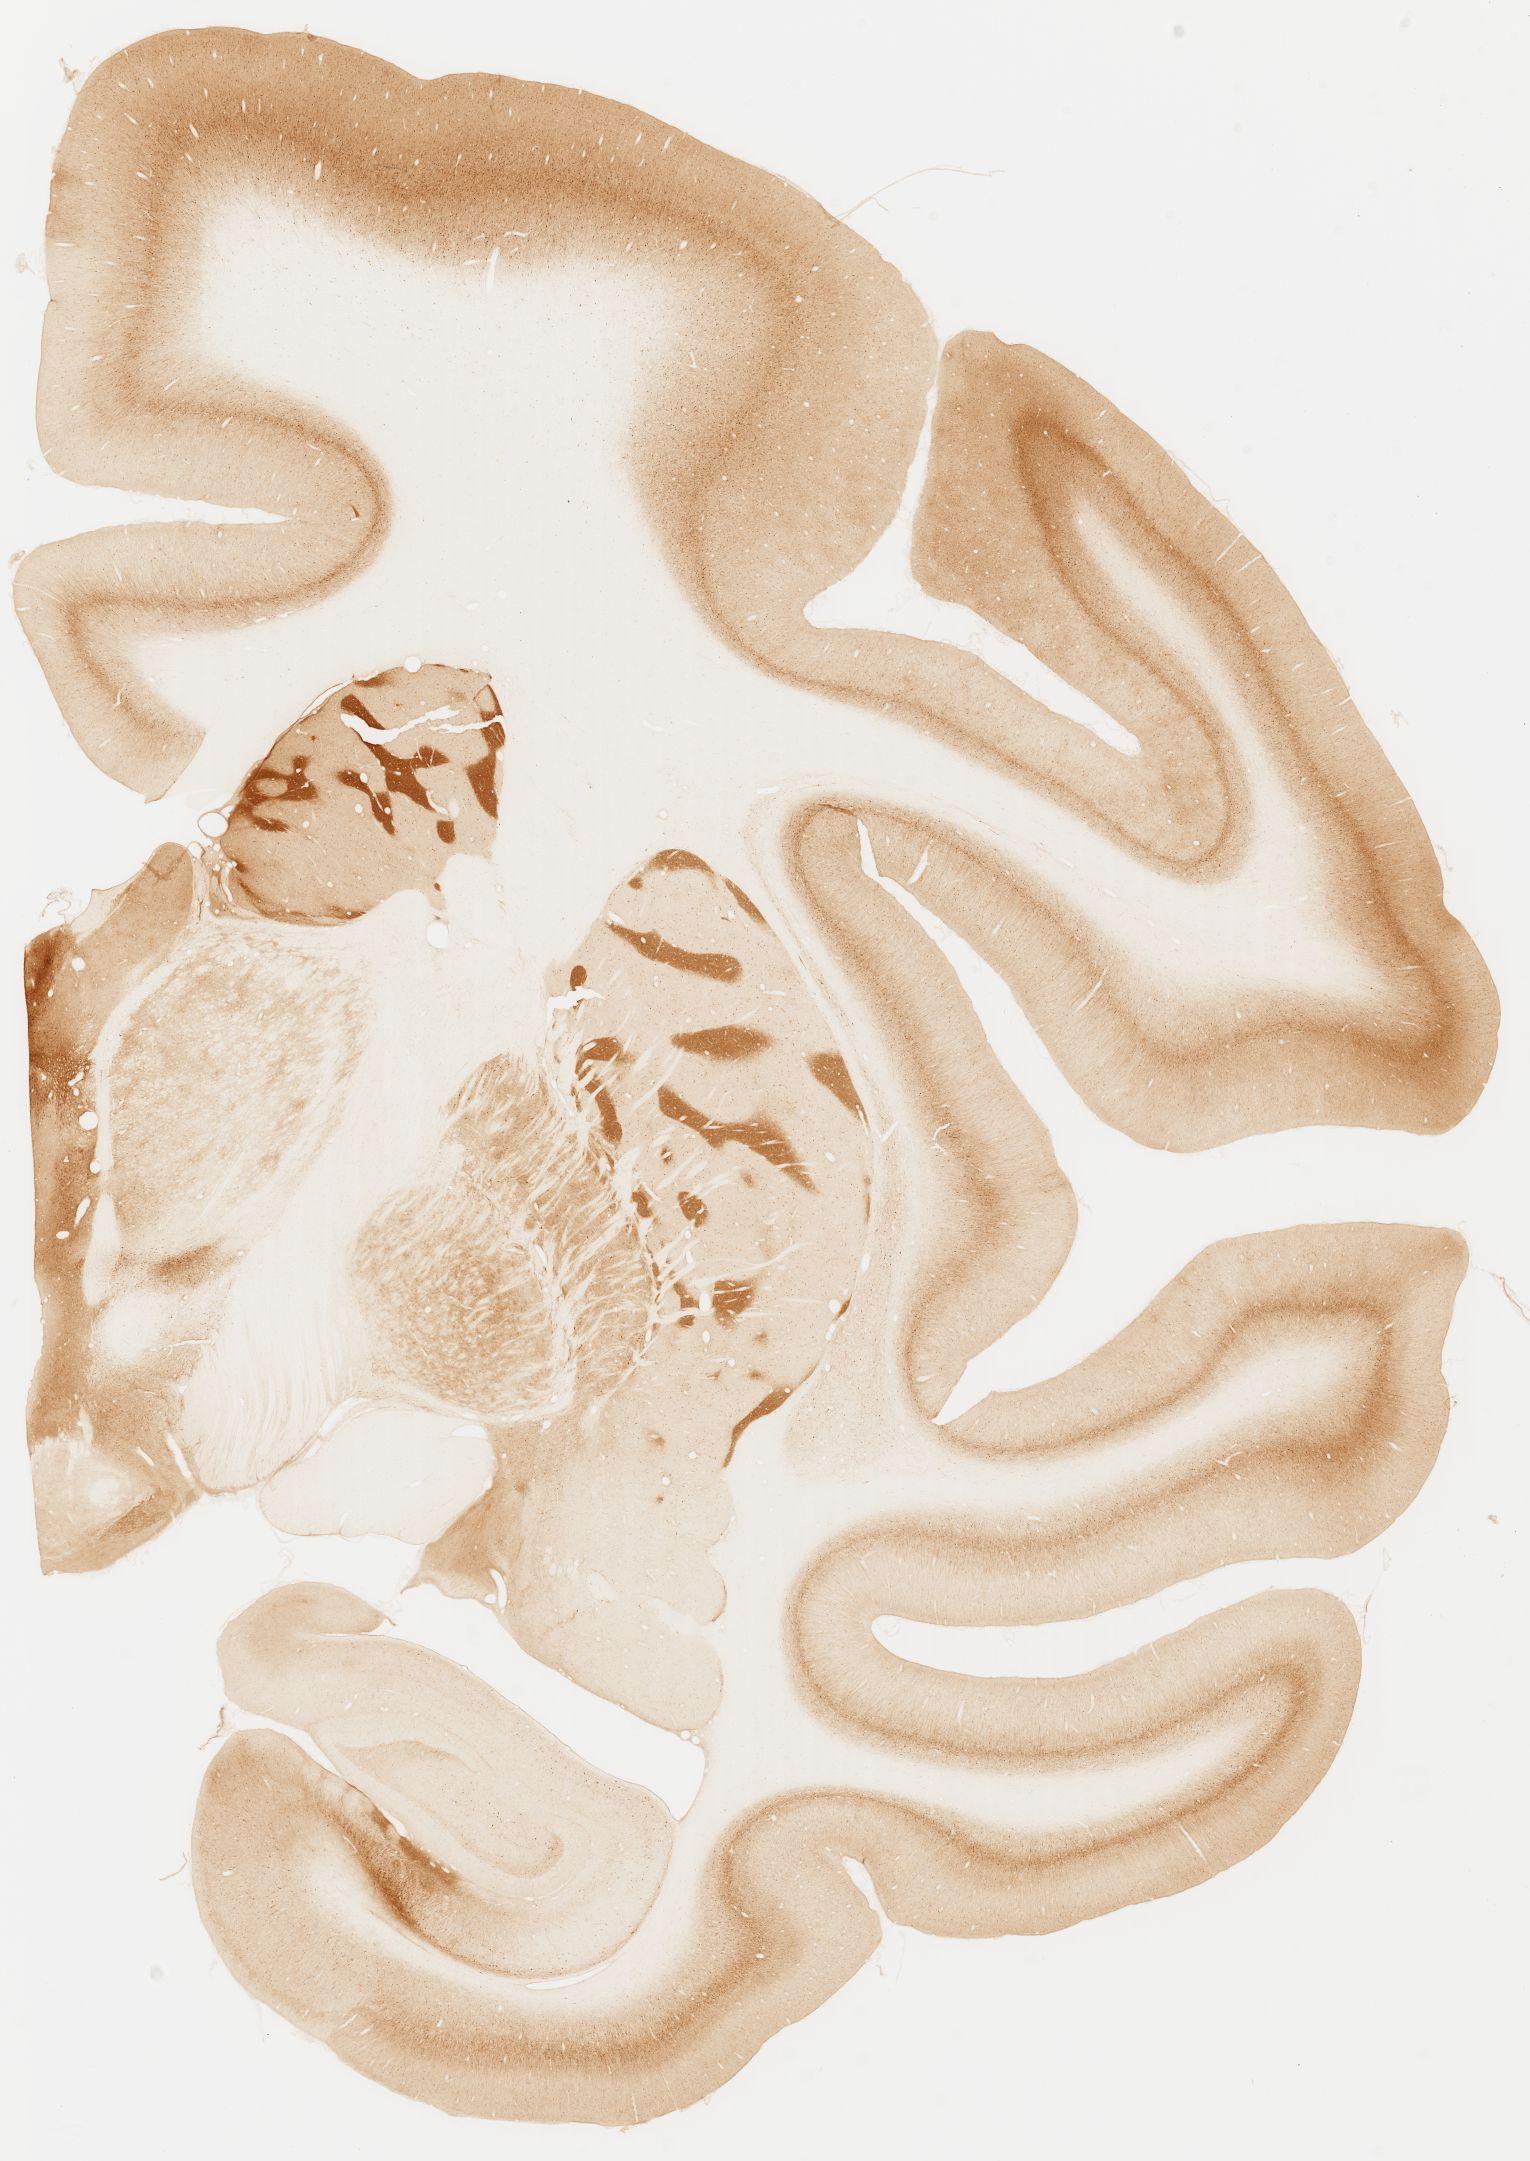

Datasets -> Macaca Fascicularis -> KChIP1, (Potassium Voltage-Gated Channel-Interacting Protein 1), coronal, immuno, Whole-Brain, adult

[ Metadata ]   ·   Source: Edward G. Jones

Displaying Sections 41 thru 80 of 92 Sections for this Dataset